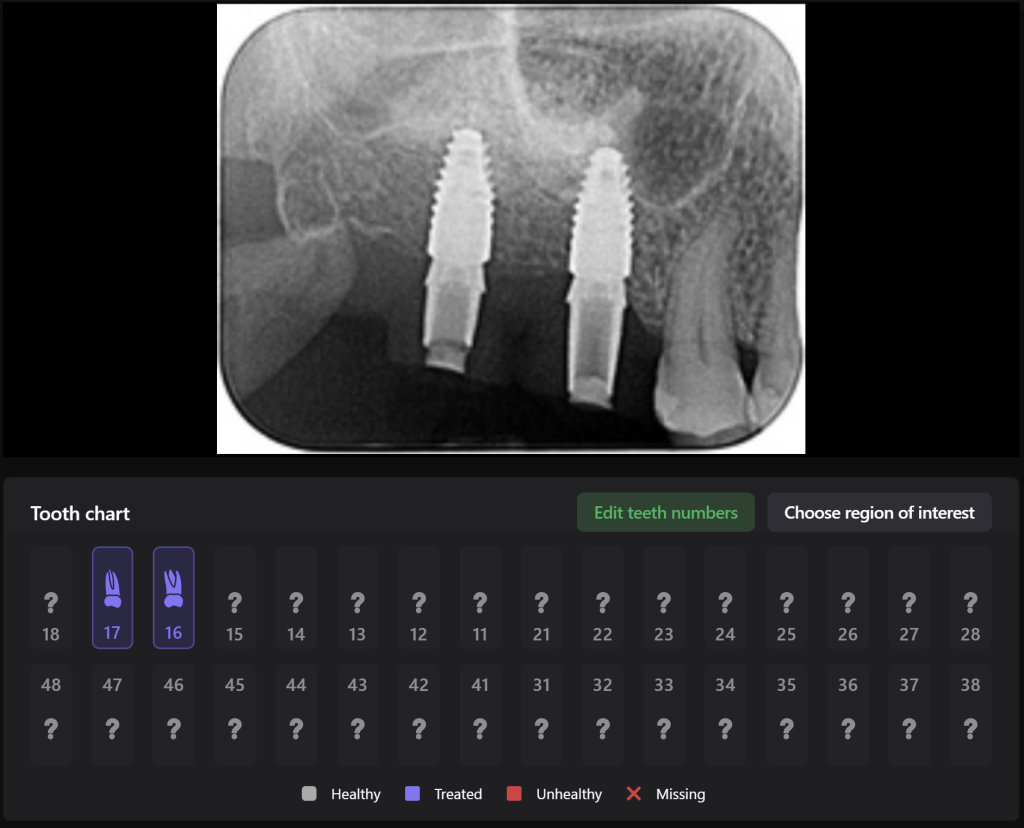

Diagnocat assists clinicians in implant treatment planning, both in guided surgery and in a classical approach. Let’s explore the capabilities of Diagnocat through a clinical case example of planning implant treatment for the replacement of missing teeth 17,16 (Universal 2,3)